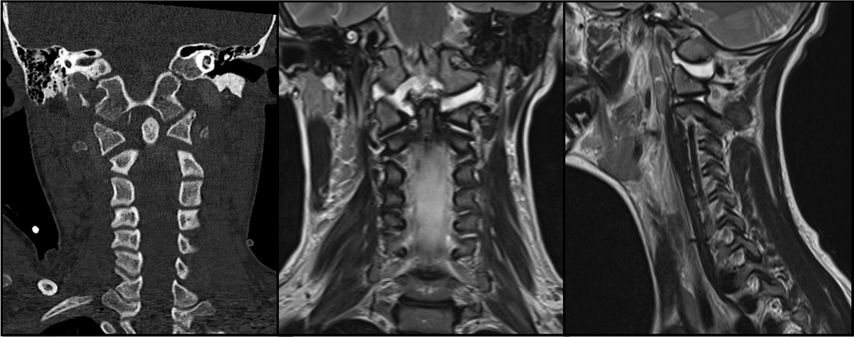

Abb. 1: CT und MRT eines pädiatrischen Patienten mit einer Typ-I-AOD und atlantoaxialer Dislokation nach Verkehrsunfall

AOD stellt die schwerste Verletzungsform im kraniozervikalen Bereich dar und ist für etwa 6–10% aller tödlichen Verletzungen der Halswirbelsäule verantwortlich. Sie tritt in über 30% der tödlichen Fälle nach Verkehrsunfällen auf und zeichnet sich durch eine hohe Letalität aus.5 Der häufigste Verletzungsmechanismus bei der kraniozervikalen Dislokation ist eine Hyperextension infolge stumpfer Gewalteinwirkung. Dabei kommt es häufig zum Riss der Membrana tectoria. Aufgrund des disproportionalen Verhältnisses zwischen Kopf und Körper sind pädiatrische Patient:innen bei Verkehrsunfällen mit hoher Geschwindigkeit besonders gefährdet. Atlantookzipitale Dissoziationen werden traditionell nach der Klassifikation von Traynelis et al.6 in drei Typen eingeteilt: Typ I beschreibt eine anteriore Verschiebung des Okziputs relativ zum Atlas, Typ II eine longitudinale Dislokation und Typ III eine posteriore Verschiebung des Okziputs gegenüber dem Atlas. Die aktuelle Harborview-Klassifikation erlaubt im Vergleich zum oberen Klassifikationssystem eine detailliertere Bewertung der Operationsindikation, da sie auf MRT-Befunden basiert und insbesondere den Grad der Dislokation berücksichtigt. Sie unterscheidet drei Verletzungstypen; TypI stellt eine stabile Verletzung dar, bei der häufig lediglich eine unilaterale Schädigung der kraniozervikalen Bänder vorliegt. In diesen Fällen ist eine konservative Behandlung in der Regel erfolgreich. Ab Typ II wird eine dorsale okzipitozervikale Fusion unter Verwendung von Plattensystemen empfohlen.